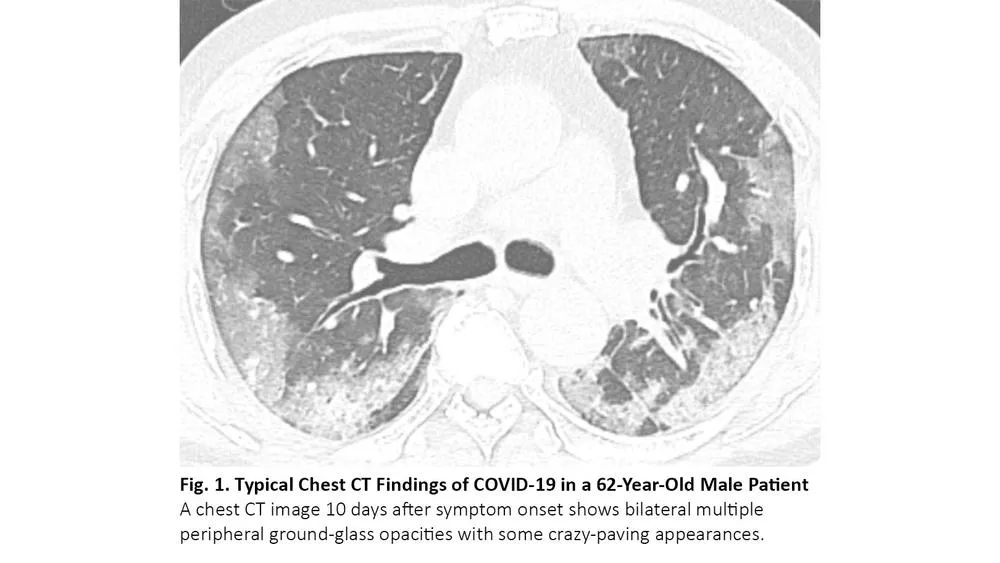

COVID-19患者的肺部CT的典型表现为双侧多发磨玻璃样影,好发于肺周3(图1)。61%~72%的COVID-19患者在症状出现后1周左右有典型CT表现,而非COVID-19患者只有不到10%人群有此类表现。4,5

图1. COVID-19患者胸部CT的典型表现

COVID-19的胸部CT可伴有局部的实质化和网状阴影(铺路石征影像表现)或其他组织性肺炎的表现,如反晕征。17% - 20%的COVID-19患者的CT与各种感染性、非感染性肺部疾病(如超敏性肺炎、肺孢子虫肺炎和弥漫性肺泡出血)难以区分(图2)。